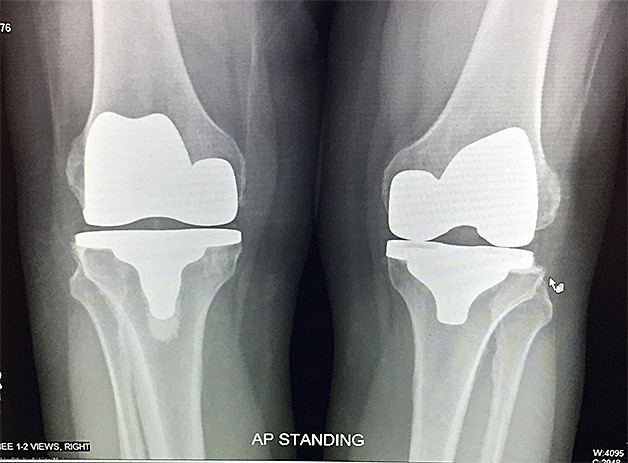

The device, called the iTotal CR, is designed specifically for each patient based on 3-D scans of the person’s knee. Surgeons take CT scan images of the knee of the patient receiving an iTotal knee replacement, which are converted into 3-D images by ConforMIS that are used to create the prosthesis.

People’s knee bones are generally not completely the same size, especially in the back, so 3-D images are especially applicable in knee replacements because they can show the intricacies in each patient’s knee bone, said Santoro.

The stock total knee replacement prosthesis used in most surgeries comes in pre-set sizes, sometimes extending too far or not covering enough of the bone, potentially leading to pain, bone bleeding and scar tissue.

More bone is also taken away during the insertion of the standard knee replacement prosthesis, leading to a greater potential for the prosthesis to loosen faster and possibly making installing a second knee replacement more complicated.